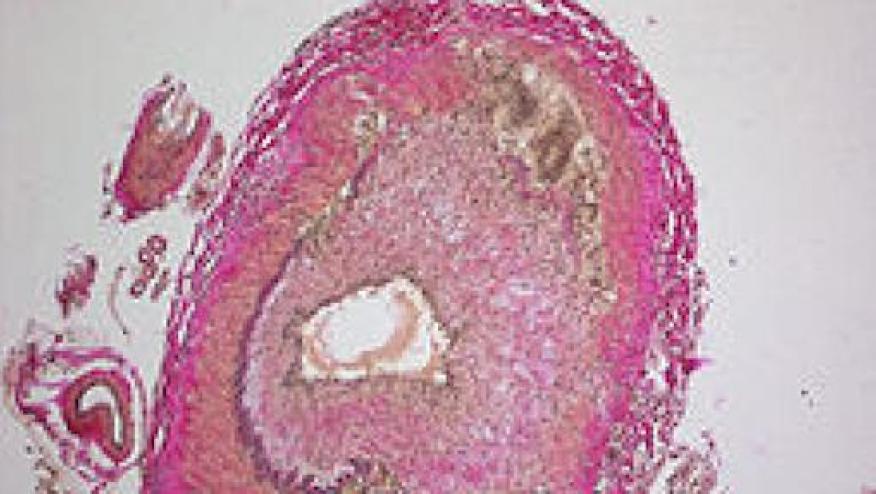

- Ultrasound of the temporal as well as axillary arteries should be considered the first imaging modality to investigate suspected GCA. They added axillary artery imaging in view of the recently published data on it. However, in practicality, very few experts are available in the United States and other places, and we as clinicians still need to rely on what is available. The halo sign may not be necessary for the diagnosis since it may be present only in acute cases.